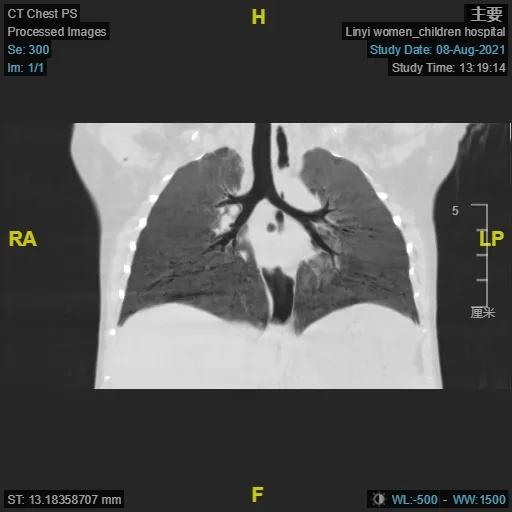

大叶性肺炎术前及术后CT对比图

(电子支气管镜、支气管肺泡灌洗术术后)